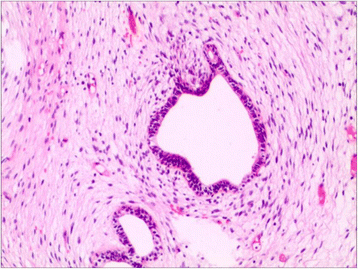

The current report presents the case of a 42-year-old male with extraordinarily salient urination difficulty that had lasted 6 months. Transrectal ultrasonography and pelvic magnetic resonance imaging demonstrated prostatic hyperplasia and cyst. PSA level was 20.65 (>4) μg/L in the patient. Transrectal prostatic biopsy revealed benign prostatic hyperplasia. He agreed to receive plasmakinetic resection of the prostate. During operation a lobulated lump was unexpectedly found on the verumontanum, with the prostate macroscopically normal. Complete tumor excision was performed and pathological assessment indicated phyllodes tumor of the verumontanum. The patient had an uneventful post-operative course and recovered well. The diagnosis, histological classification, treatment, and prognosis of this case are presented. It is necessary to perform cystoscopy to exclude verumontanum tumor even when all imaging examinations indicate prostate hyperplasia, especially in young males. Virtual slides: The virtual slide(s) for this article can be found here: http://www.diagnosticpathology.diagnomx.eu/vs/1868931661161758.